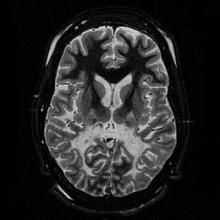

腎上腺腦白質失養症,又名ALD,是一種腦內去髓鞘化白質化的遺傳病,其通常分作兒童型腦白質化、青少年大腦型、腎上腺脊髓性神經病變型及女性異型合子病徵基因型。患者細胞的過氧化體在代謝較長的鏈脂肪酸時產生異常,尤其是C24、C26長鏈脂肪酸會異常堆積在大腦的白質和腎上腺的皮質內,進而侵蝕患者腦神經系統的髓鞘質,造成患者的髓鞘脫失,腦部的神經細胞因此就會被摧毀,進而妨礙神經的傳導。美國男性發生腎上腺腦白質失養症的機率為1:42,000;加上女性異合子基因型的發生率是1:16,800。而最近的報告則顯示為1/17000至1/25000。